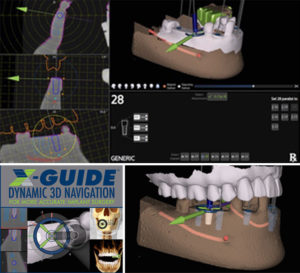

Browse our specialized Calibration In Dynamic Navigation Surgery In Implamt portfolio with numerous expertly curated photographs. optimized for both digital and print applications across multiple platforms. providing reliable visual resources for business and academic use. Each Calibration In Dynamic Navigation Surgery In Implamt image is carefully selected for superior visual impact and professional quality. Perfect for marketing materials, corporate presentations, advertising campaigns, and professional publications All Calibration In Dynamic Navigation Surgery In Implamt images are available in high resolution with professional-grade quality, optimized for both digital and print applications, and include comprehensive metadata for easy organization and usage. Our Calibration In Dynamic Navigation Surgery In Implamt collection provides reliable visual resources for business presentations and marketing materials. Whether for commercial projects or personal use, our Calibration In Dynamic Navigation Surgery In Implamt collection delivers consistent excellence. The Calibration In Dynamic Navigation Surgery In Implamt archive serves professionals, educators, and creatives across diverse industries. Regular updates keep the Calibration In Dynamic Navigation Surgery In Implamt collection current with contemporary trends and styles. Advanced search capabilities make finding the perfect Calibration In Dynamic Navigation Surgery In Implamt image effortless and efficient. Multiple resolution options ensure optimal performance across different platforms and applications.